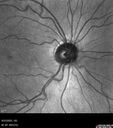

Optic Disc Drusen in a child (non Calcified)33 viewsFluorescein angiography shows no leakage

Optic Disc Drusen in a child (non Calcified)28 viewsFluorescein angiography shows no leakage

Optic Disc Drusen in a child (non Calcified)27 viewsFluorescein angiography shows no leakage

Optic Disc Drusen in a child (non Calcified)26 viewsFluorescein angiography shows no leakage

Optic Disc Drusen in a child (non Calcified)25 viewsFluorescein angiography shows no leakage

Optic Disc Drusen in a child (non Calcified)24 viewsFluorescein angiography shows no leakage

Optic Disc Drusen in a child (non Calcified)23 viewsFluorescein angiography shows no leakage

Optic Disc Drusen in a child (non Calcified)21 viewsFluorescein angiography shows no leakage